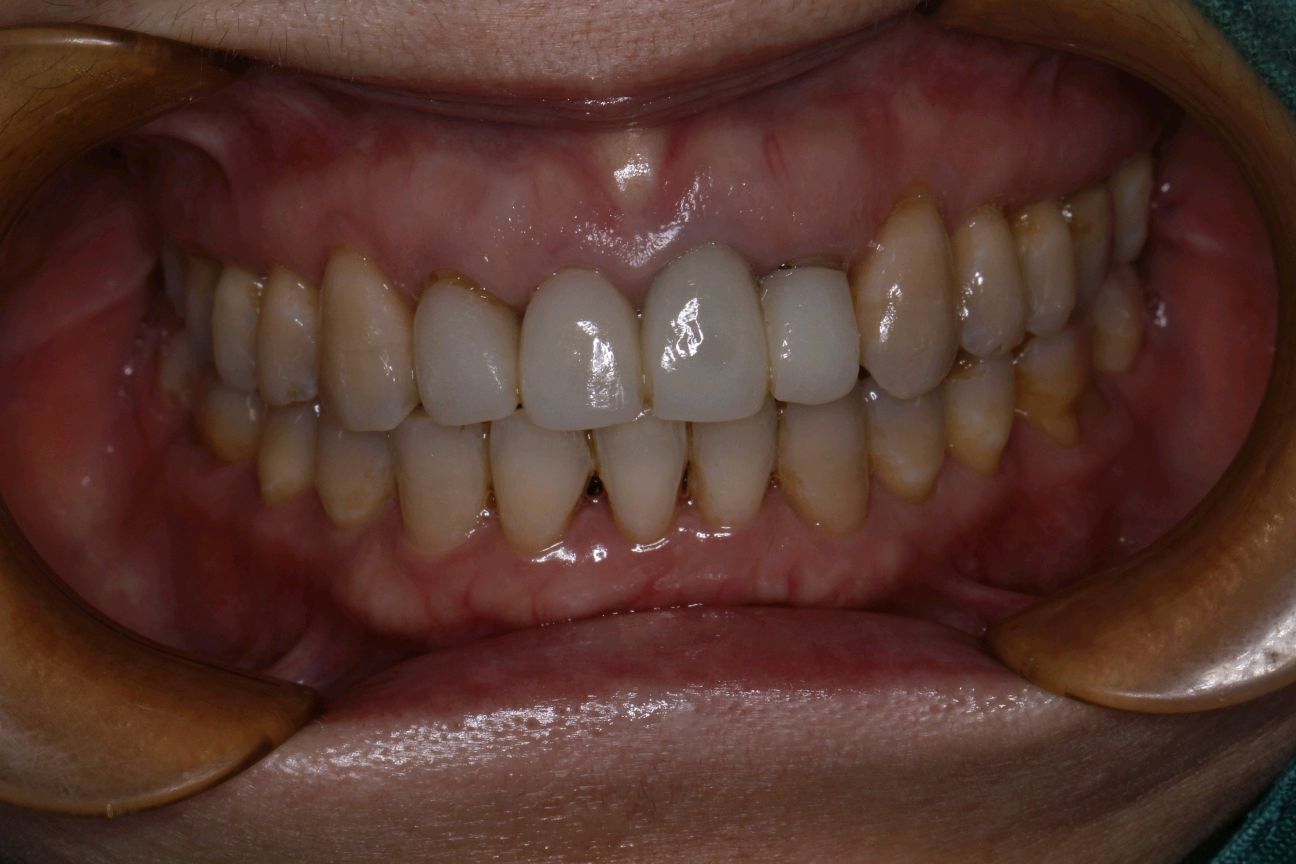

患者女,三十岁,11、12、21,22牙已行根管治疗+烤瓷全冠修复。由于长时间烤瓷牙的佩戴,导致牙龈边缘发黑,边缘不密合,颈缘处牙龈组织出现"黑线"。腭侧部分也出现了崩瓷的现象。对于这种情况,建议患者尽早重新修复,避免二次伤害。患者最终选择重新修复,也给出患者合理的方案,患者选全瓷冠修复,与今日佩戴完毕。边缘密合度良好,形态色泽自然美观,患者满意。

术前